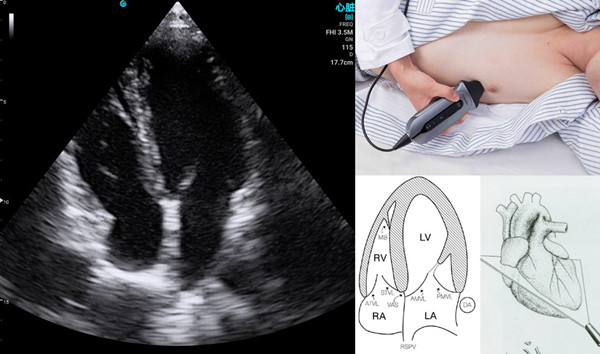

Real-Time Visualization

Healthcare providers can use handheld ultrasound devices to show patients real-time images of their internal organs and structures. This visual aid helps patients understand their conditions better and appreciate the diagnostic process. Improved understanding often leads to increased trust and confidence in the care they receive.

Bedside and Point-of-Care Imaging

Patients no longer need to be transported to different parts of the hospital for imaging. Handheld ultrasound devices can be brought directly to the patient, whether they are in the emergency room, intensive care unit, or even in an outpatient setting. This reduces the stress and physical discomfort associated with moving between departments.